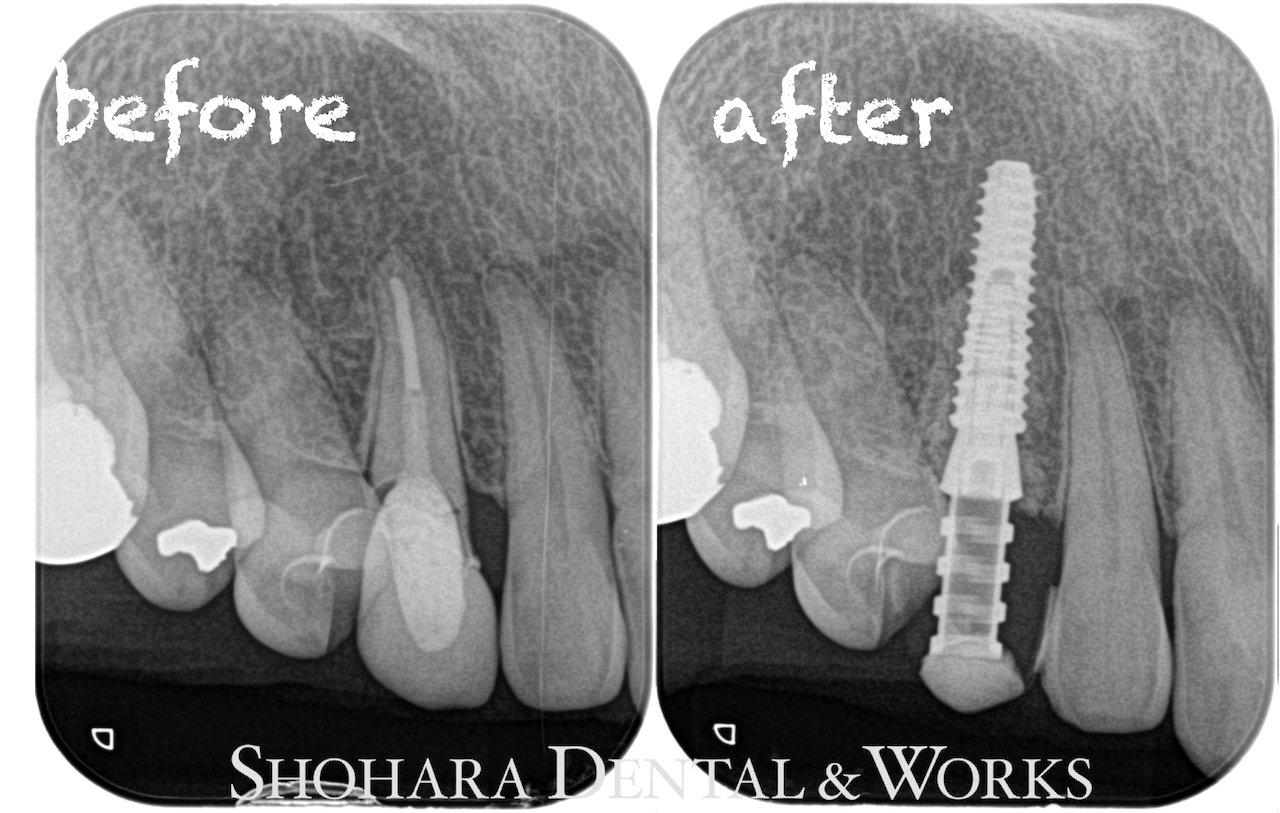

2025年9月に右上犬歯ののセラミックの歯が脱離で来院されました。

CTでの診査の結果、歯根の一部が破折しており、保存困難と診断しました。

手術当日、保存困難な犬歯を抜歯して、即時でサージカルステントを用いてインプラントを埋入し、その日に仮歯を装着しました。

その後、3ヶ月の待機期間をおいて、口腔内スキャナーで印象採得を行い、2026年1月にジルコニアセラミックスの上部構造を装着しました。